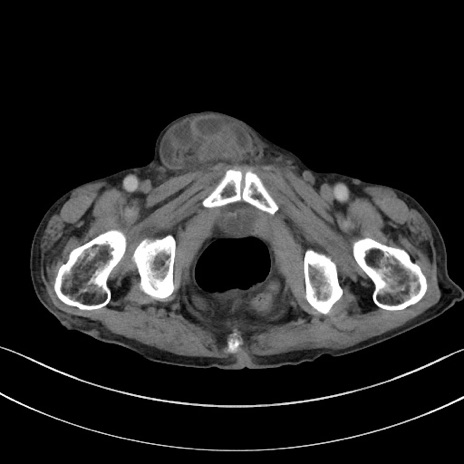

症例3(横断像)

【症例】 70歳代男性

【主訴】右鼠径部腫瘤、疼痛

【現病歴】本日朝より上記主訴あり、受診。

【既往歴】膀胱癌にて膀胱全摘、両側尿管皮膚瘻

【データ】WBC 5600、CRP 0.56